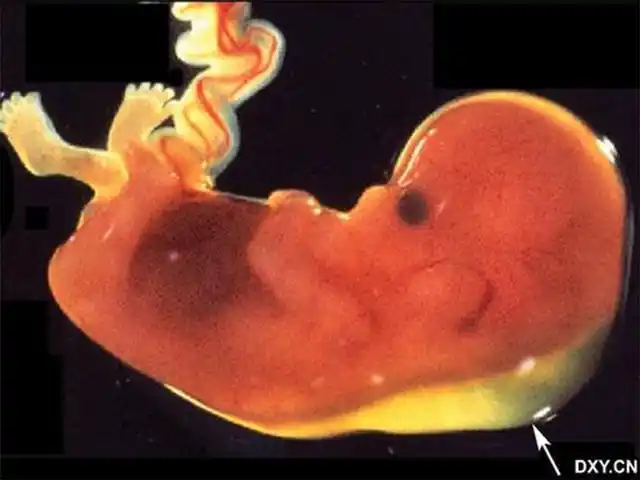

皮肤开始出现毛囊,肝脏开始活动头部占胎儿身长的一半外部生殖器官